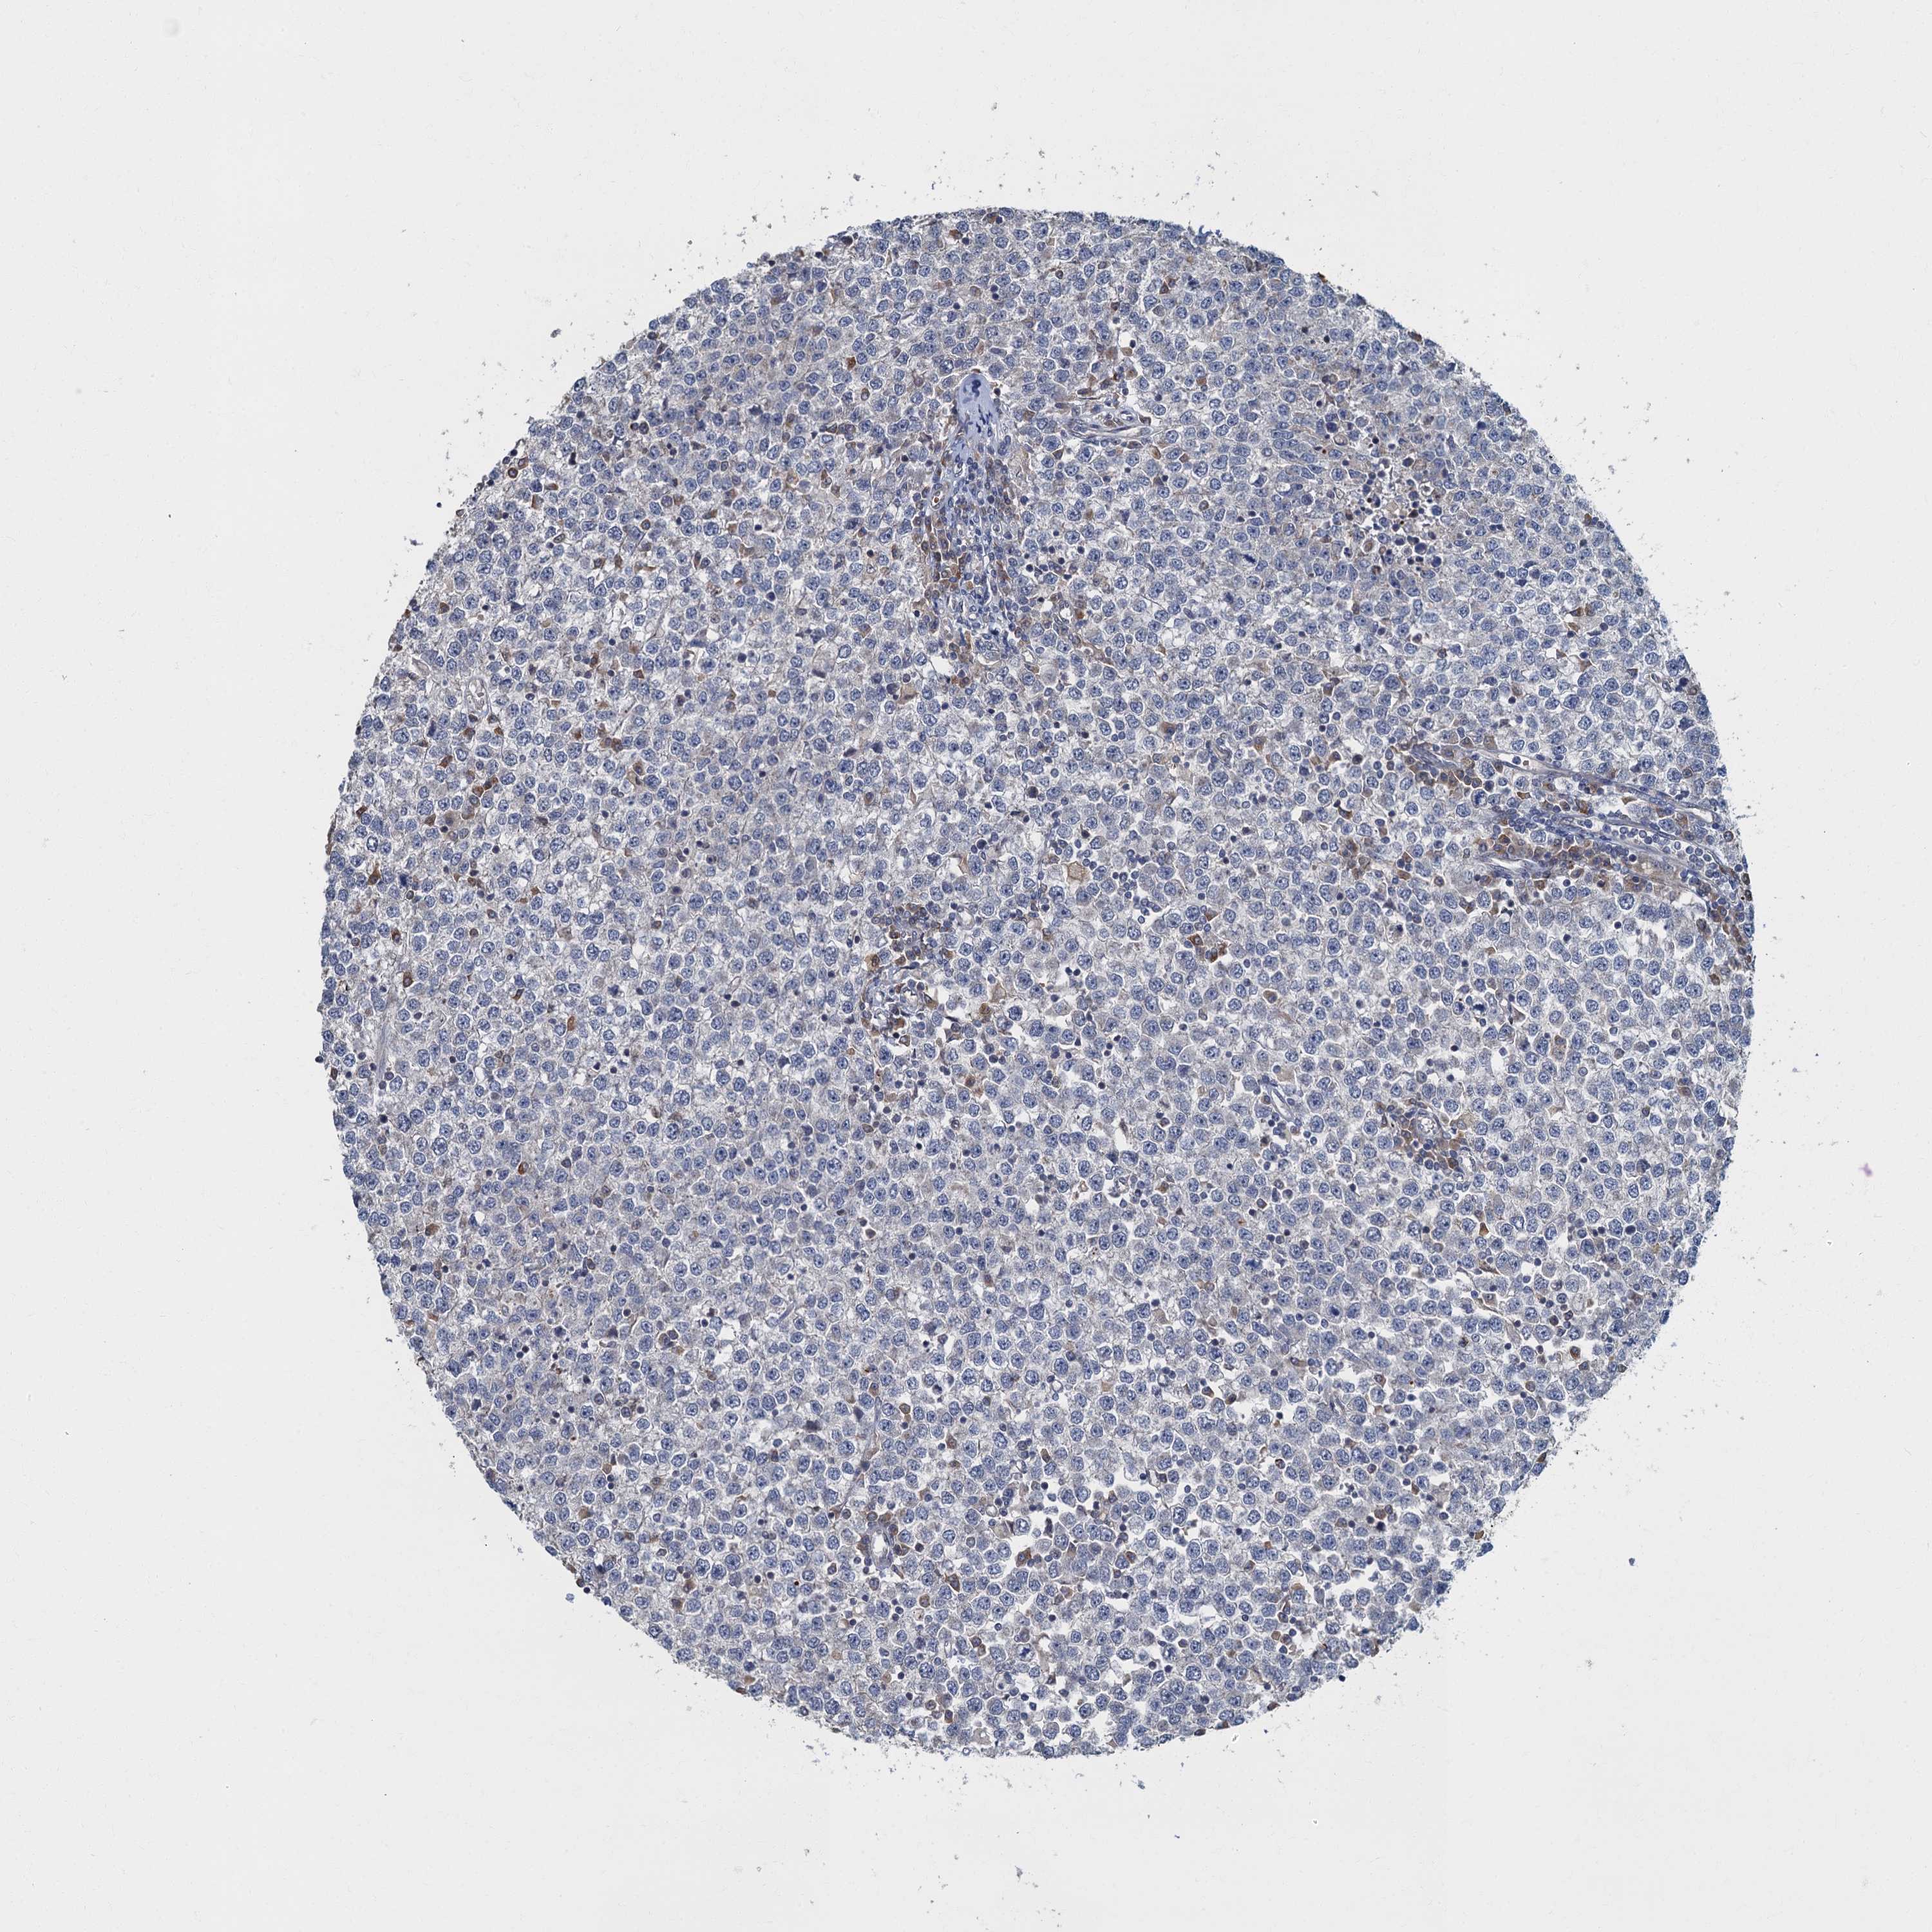

TESTIS CANCER - Protein expressioni

A mouse-over function shows sample information and annotation data. Click on an image to view it in a full screen mode. Samples can be filtered based on level of antibody staining by selecting one or several of the following categories: high, medium, low and not detected. The assay and annotation is described here.

Note that samples used for immunohistochemistry by the Human Protein Atlas do not correspond to samples in the TCGA dataset.

Antibody stainingi

Antibody staining in the annotated cell types in the current human tissue is reported as not detected, low, medium, or high, based on conventional immunohistochemistry profiling in selected tissues. This score is based on the combination of the staining intensity and fraction of stained cells.

Each image is clickable and will lead to virtual microscopy that enables deeper exploration of all samples and also displays staining intensity scores, fraction scores and subcellular localization as well as patient and tissue information for each sample.

Antibody HPA039951

Staining

High

Medium

Low

Not detected

Intensity

Strong

Moderate

Weak

Negative

Quantity

>75%

75%-25%

<25%

None

Location

Nuclear

Cytoplasmic/membranous

Cytoplasmic/membranous,nuclear

Carcinoma, Embryonal, NOS

Seminoma, NOS

Urothelial carcinoma, High grade